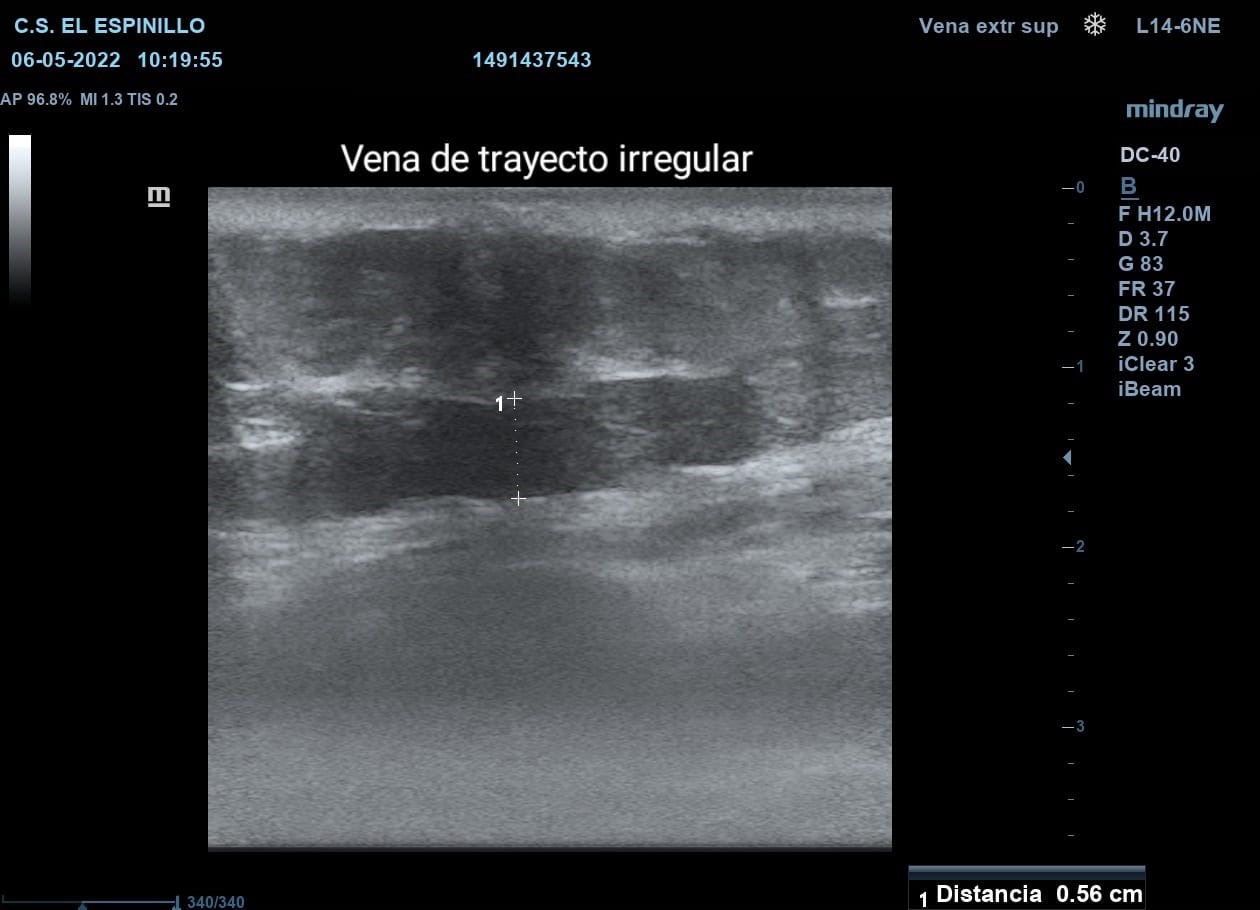

Hallazgos ecográficos

En la ecografía se observa estructura tubular de 0,56 cm de grosor que va desde pliegue mamario hasta pared abdominal anterolateral izquierda. Se observa ausencia de compresibilidad de la vena. No capta Doppler. Imágenes sugestivas de trombosis superficial.